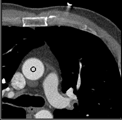

Samples for ascending aorta detection (black circle):

Cluster of candidate points in the ascending aorta.